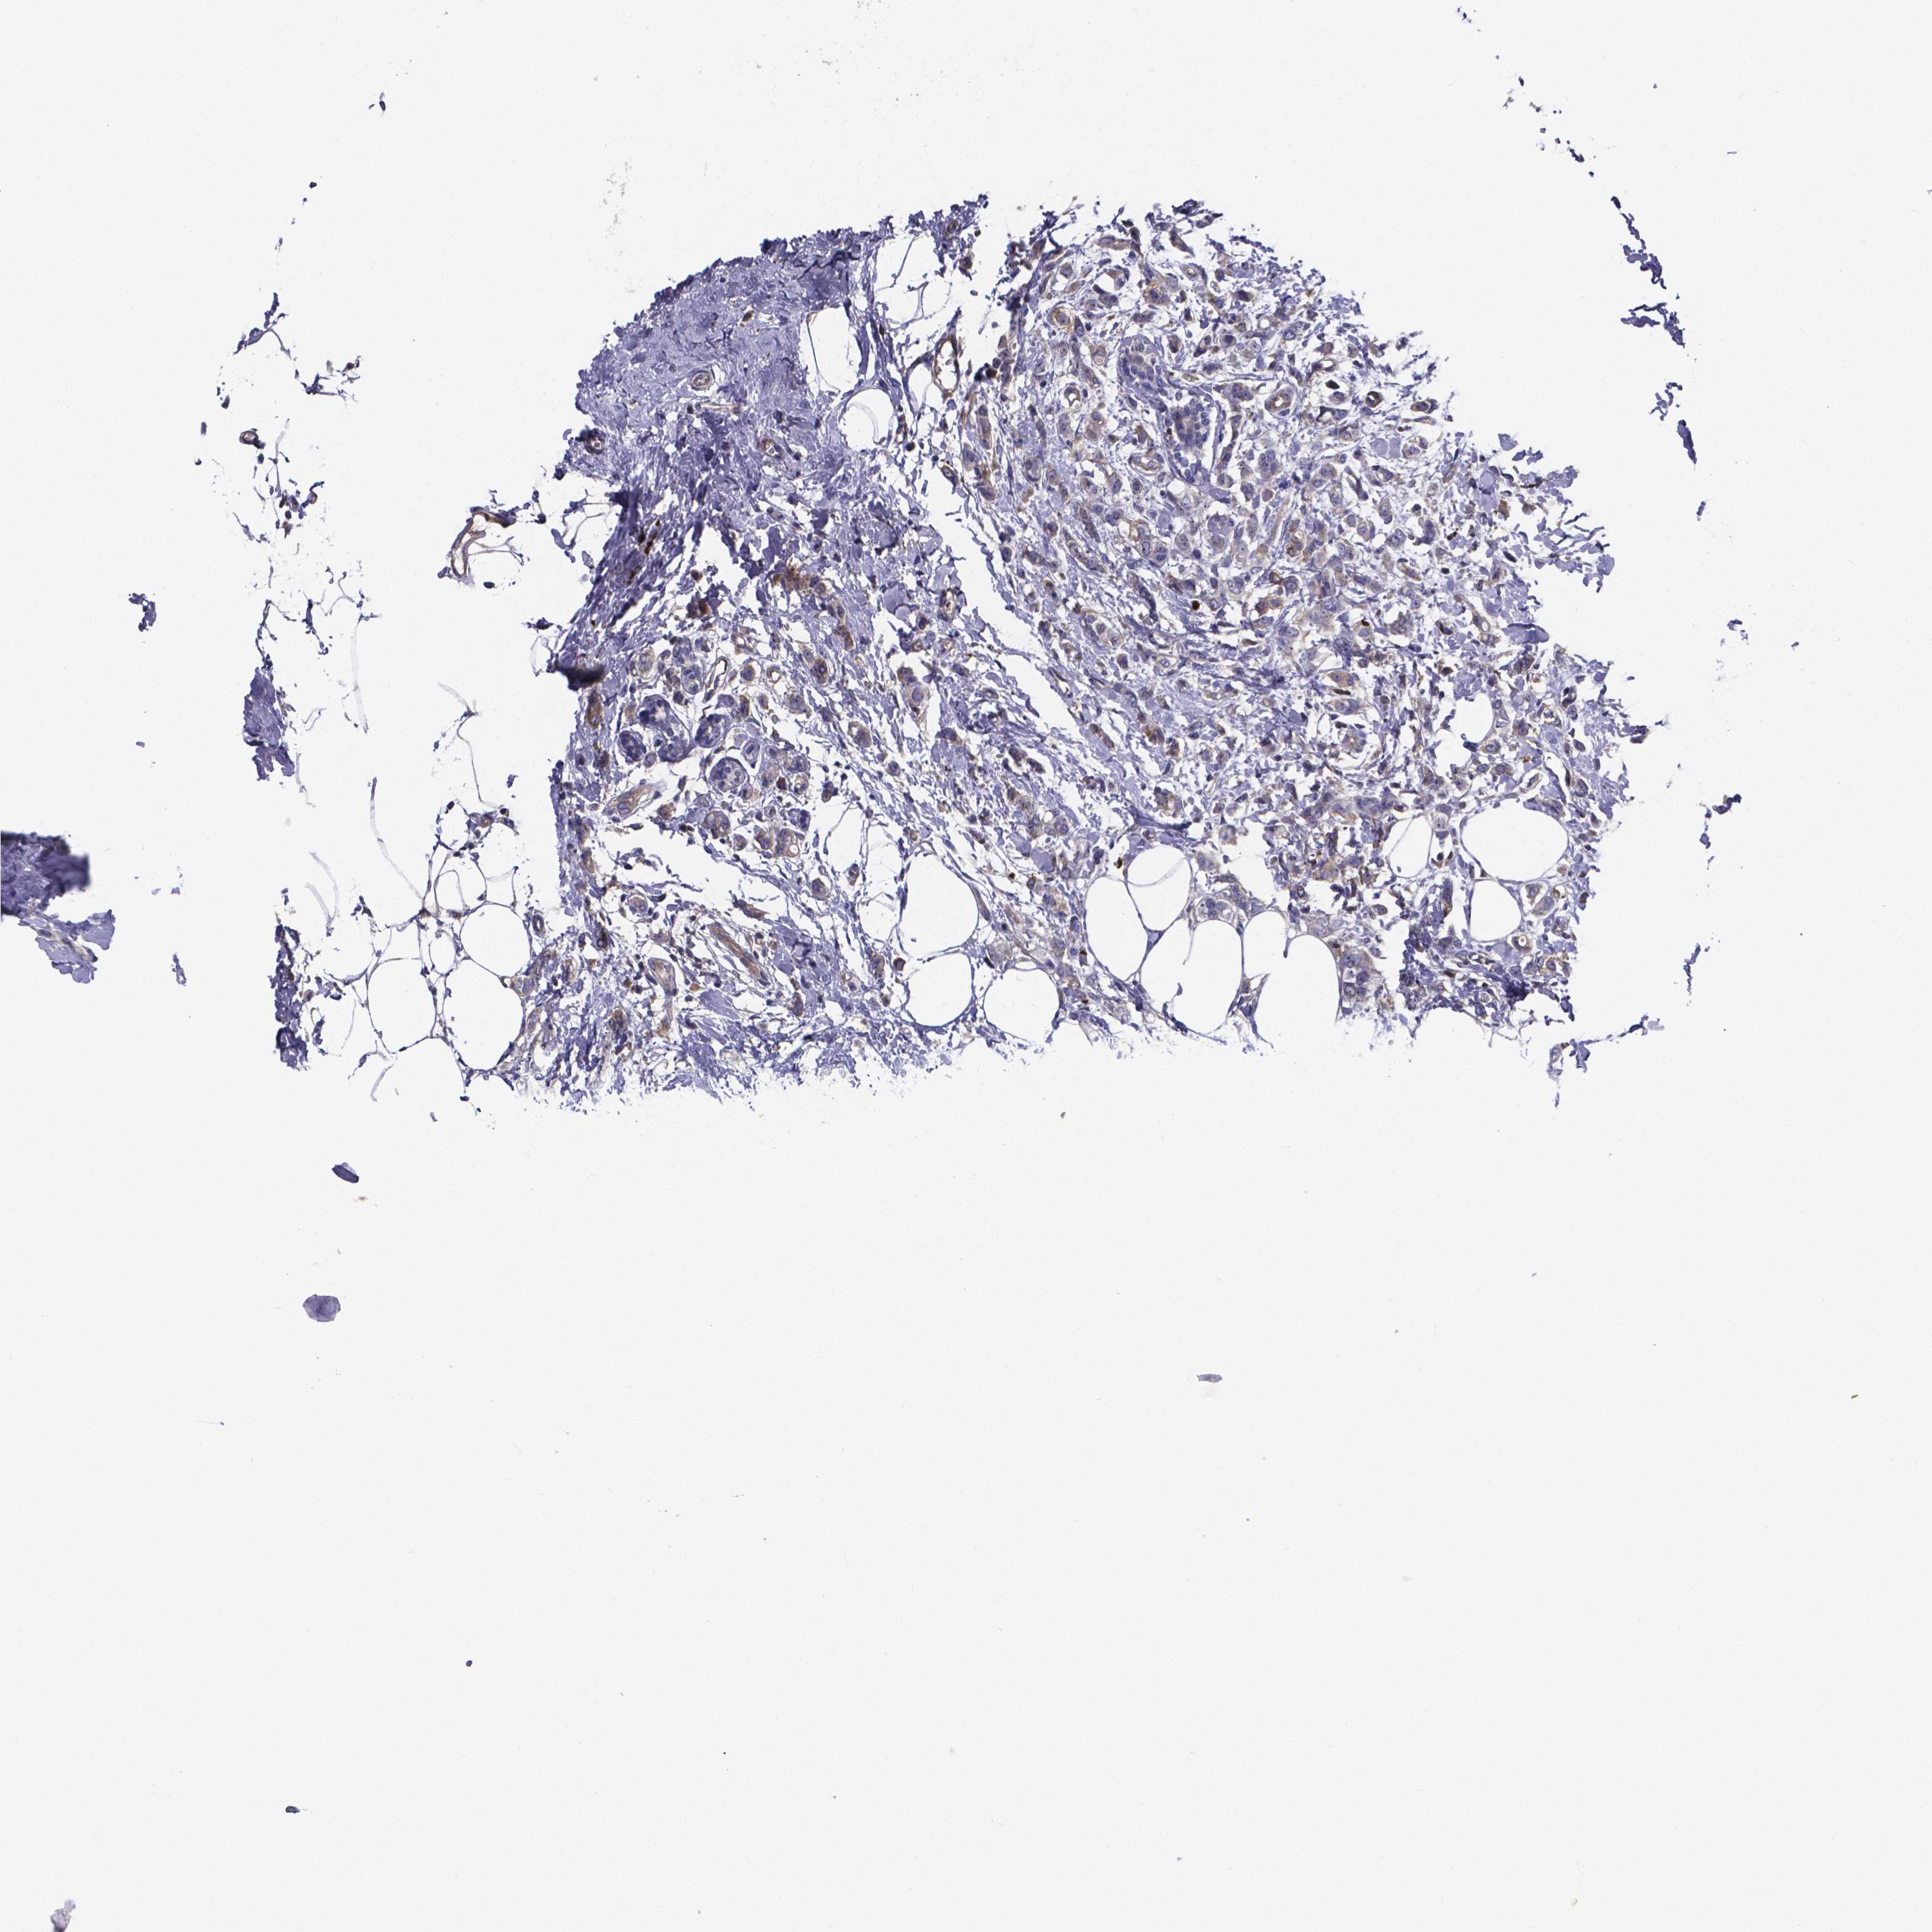

BRCA TCGA BRCA VALIDATION PROTEIN EXPRESSION